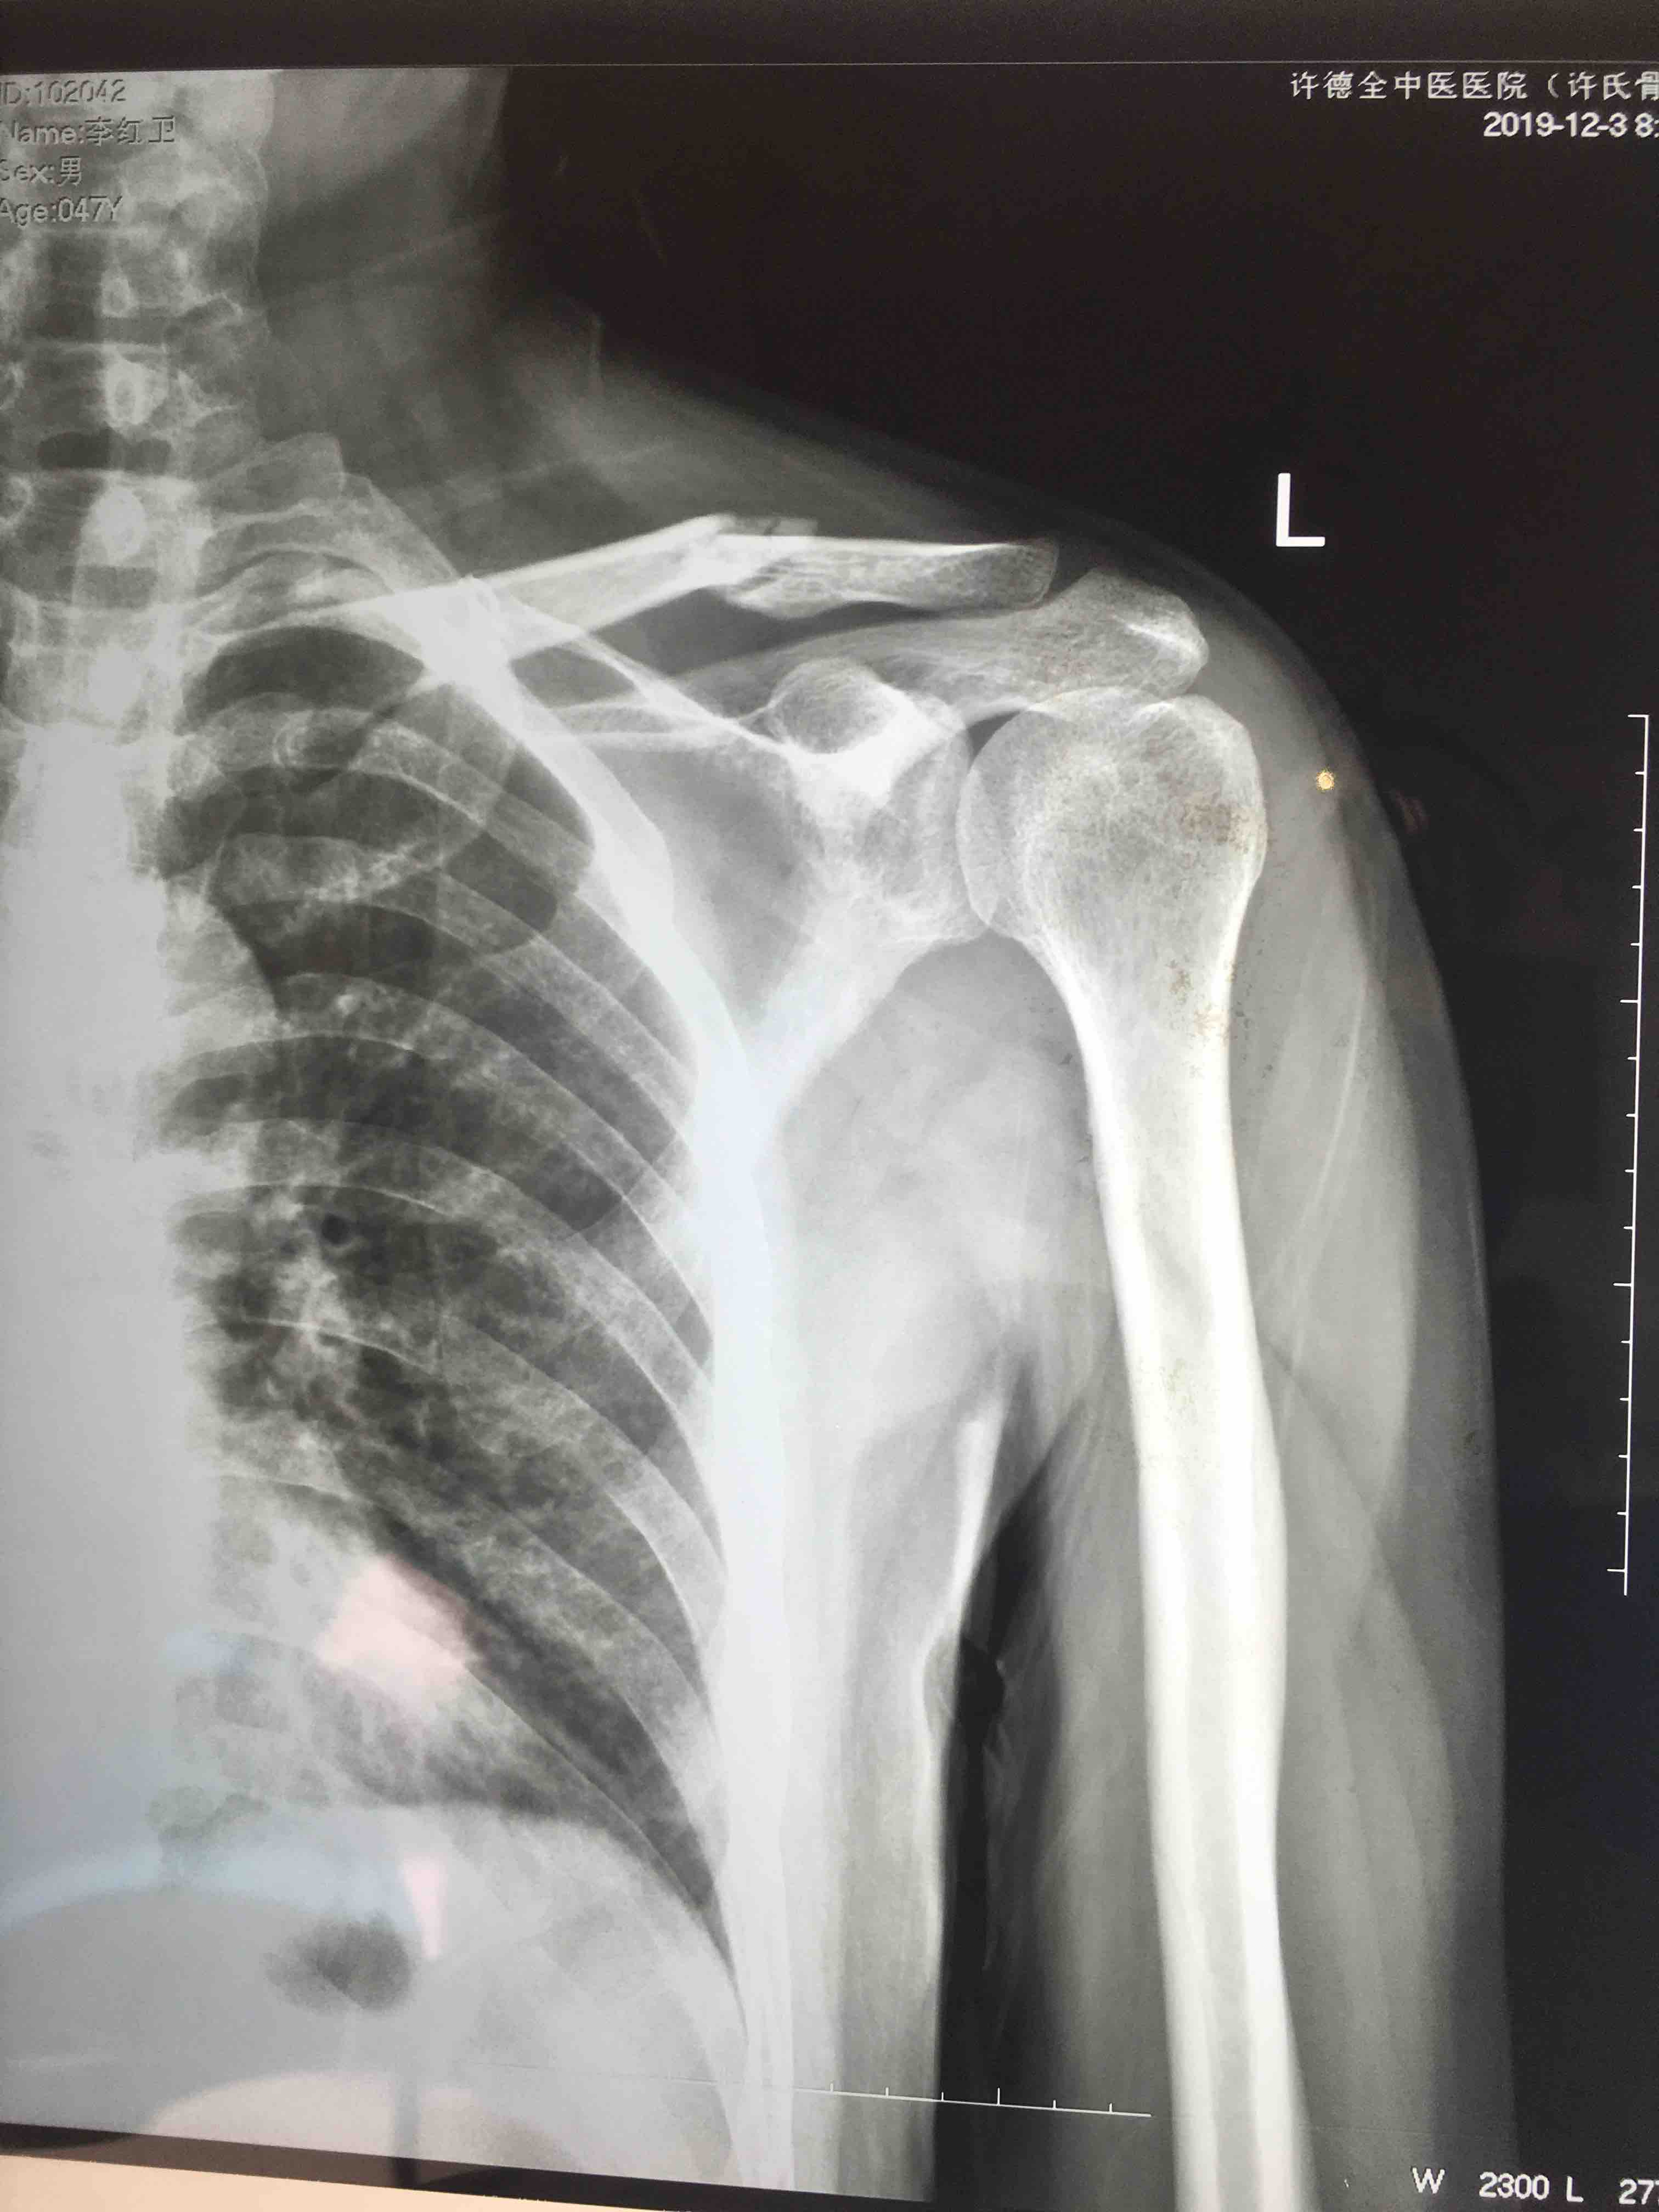

锁骨骨折(切复内固定术)

骨折 锁骨骨折

摔伤后左肩肿痛,活动受限1小时入院。既往身体健康,无不良嗜好。

生命体征平稳,心肺复未见异常。左肩部皮色皮温正常,压痛及纵向叩击痛阳性,肩关节活动受限,末梢血运感觉正常。

诊断左锁骨骨折在臂丛麻醉下切复内固定术,术后抗炎消肿等处理。